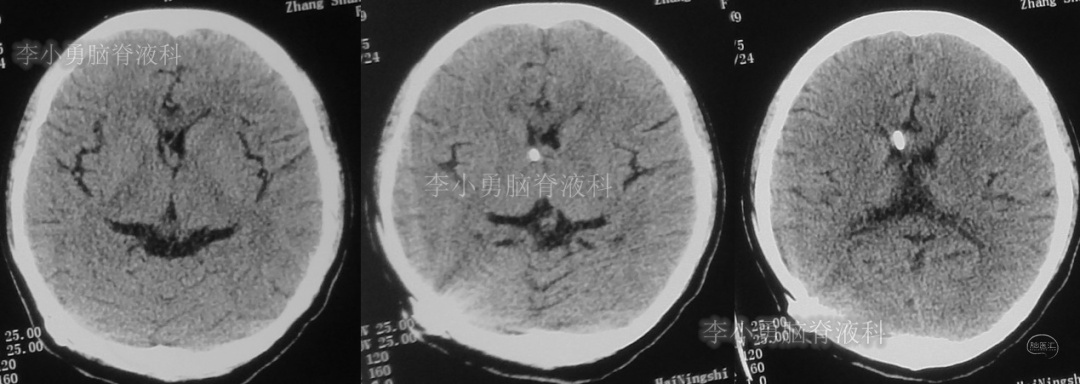

此后1个多月(2019年11月4日到2019年12月16日),患者意识一直无改善,一直呈模糊状态,多次复查头颅CT(图-12至图-20)见脑室大小反复变化不定,医生根据CT结果等反复多次调节分流泵压力(具体过程家属回忆不起)。但患者病情无好转却逐渐加重,逐渐不能咀嚼、吞咽及进食,卧床不起。

图-12:2019年11月8日头颅CT

图-13:2019年11月16日头颅CT

图-14:2019年11月19日头颅CT

图-15:2019年12月3日头颅CT

图-16:2019年12月10日头颅CT

图-17:2019年12月12日头颅CT

图-18:2019年12月13日头颅CT

图-19:2019年12月14日头颅CT

图-20:2019年12月16日头颅CT